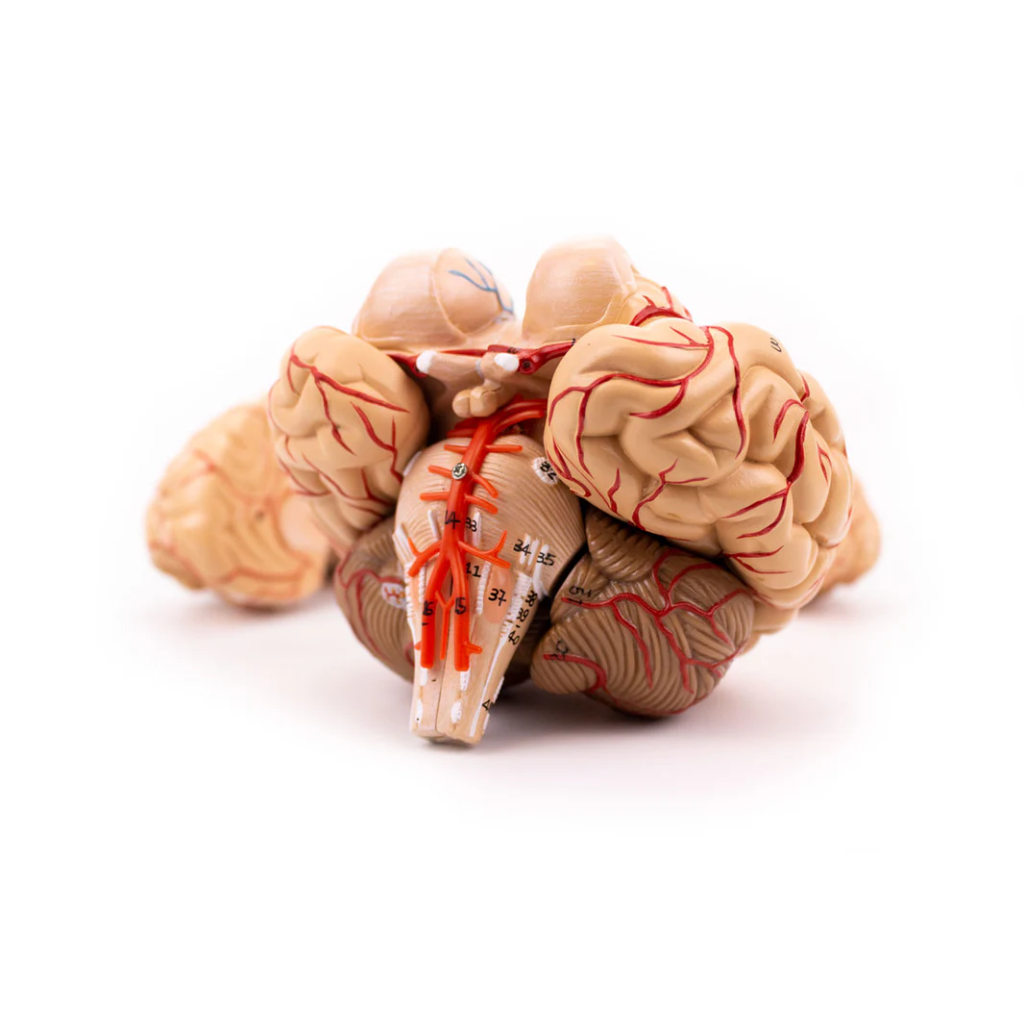

3B Scientific

Encéfalo de lujo con arterias en la base de la cabeza, desmontable en 8 piezas

Precio de venta$22,344.58

3B Scientific

Cerebro de Lujo con Arterias, desmontable en 9 piezas - 3B Smart Anatomy

Precio de venta$18,177.53